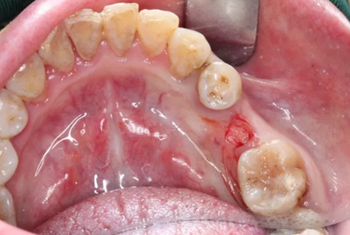

2.使用牙齦環(huán)切刀施行不翻瓣手術(shù),創(chuàng)傷小,保護(hù)患者牙齦軟組織形態(tài)。

1.試戴臨時(shí)基臺(tái),觀看咬頜位置并且記錄,將基臺(tái)在口外進(jìn)行調(diào)磨。

4.醫(yī)生將臨時(shí)修復(fù)體與臨時(shí)基臺(tái)粘接后并且將其戴到患者口內(nèi)。

5.臨時(shí)修復(fù)體在患者口內(nèi)就位后的狀況。醫(yī)生將咬頜紙放入患者口內(nèi)將臨時(shí)修復(fù)體進(jìn)行觀察調(diào)整。幾乎沒有經(jīng)歷調(diào)磨即可準(zhǔn)確就位。